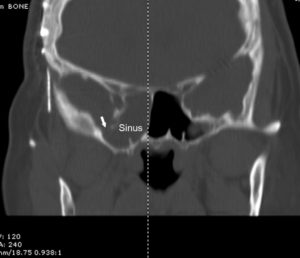

Cerebrospinal fluid (csf) is a fluid that cushions the brain Nasal csf leaks are caused by small, sometimes microscopic breaks in the barrier between the brain and roof of the sinuses A cerebrospinal fluid leak can cause symptoms like headaches, nasal drainage, and tinnitus If you have a persistent headache lasting a week or experience csf leaking from your ears or nose, see a healthcare provider

Csf leak may also be spontaneous, due to intracranial tumors, idiopathic intracranial hypertension (iih), or congenital skull defects. Csf rhinorrhea is a condition where cerebrospinal fluid (csf) leaks through the nose Normally cerebrospinal fluid is confined to the space around the brain and spinal cord Due to its close proximity to the sinus and nasal cavity, any opening will allow csf to leak into it and then drain out through the nose